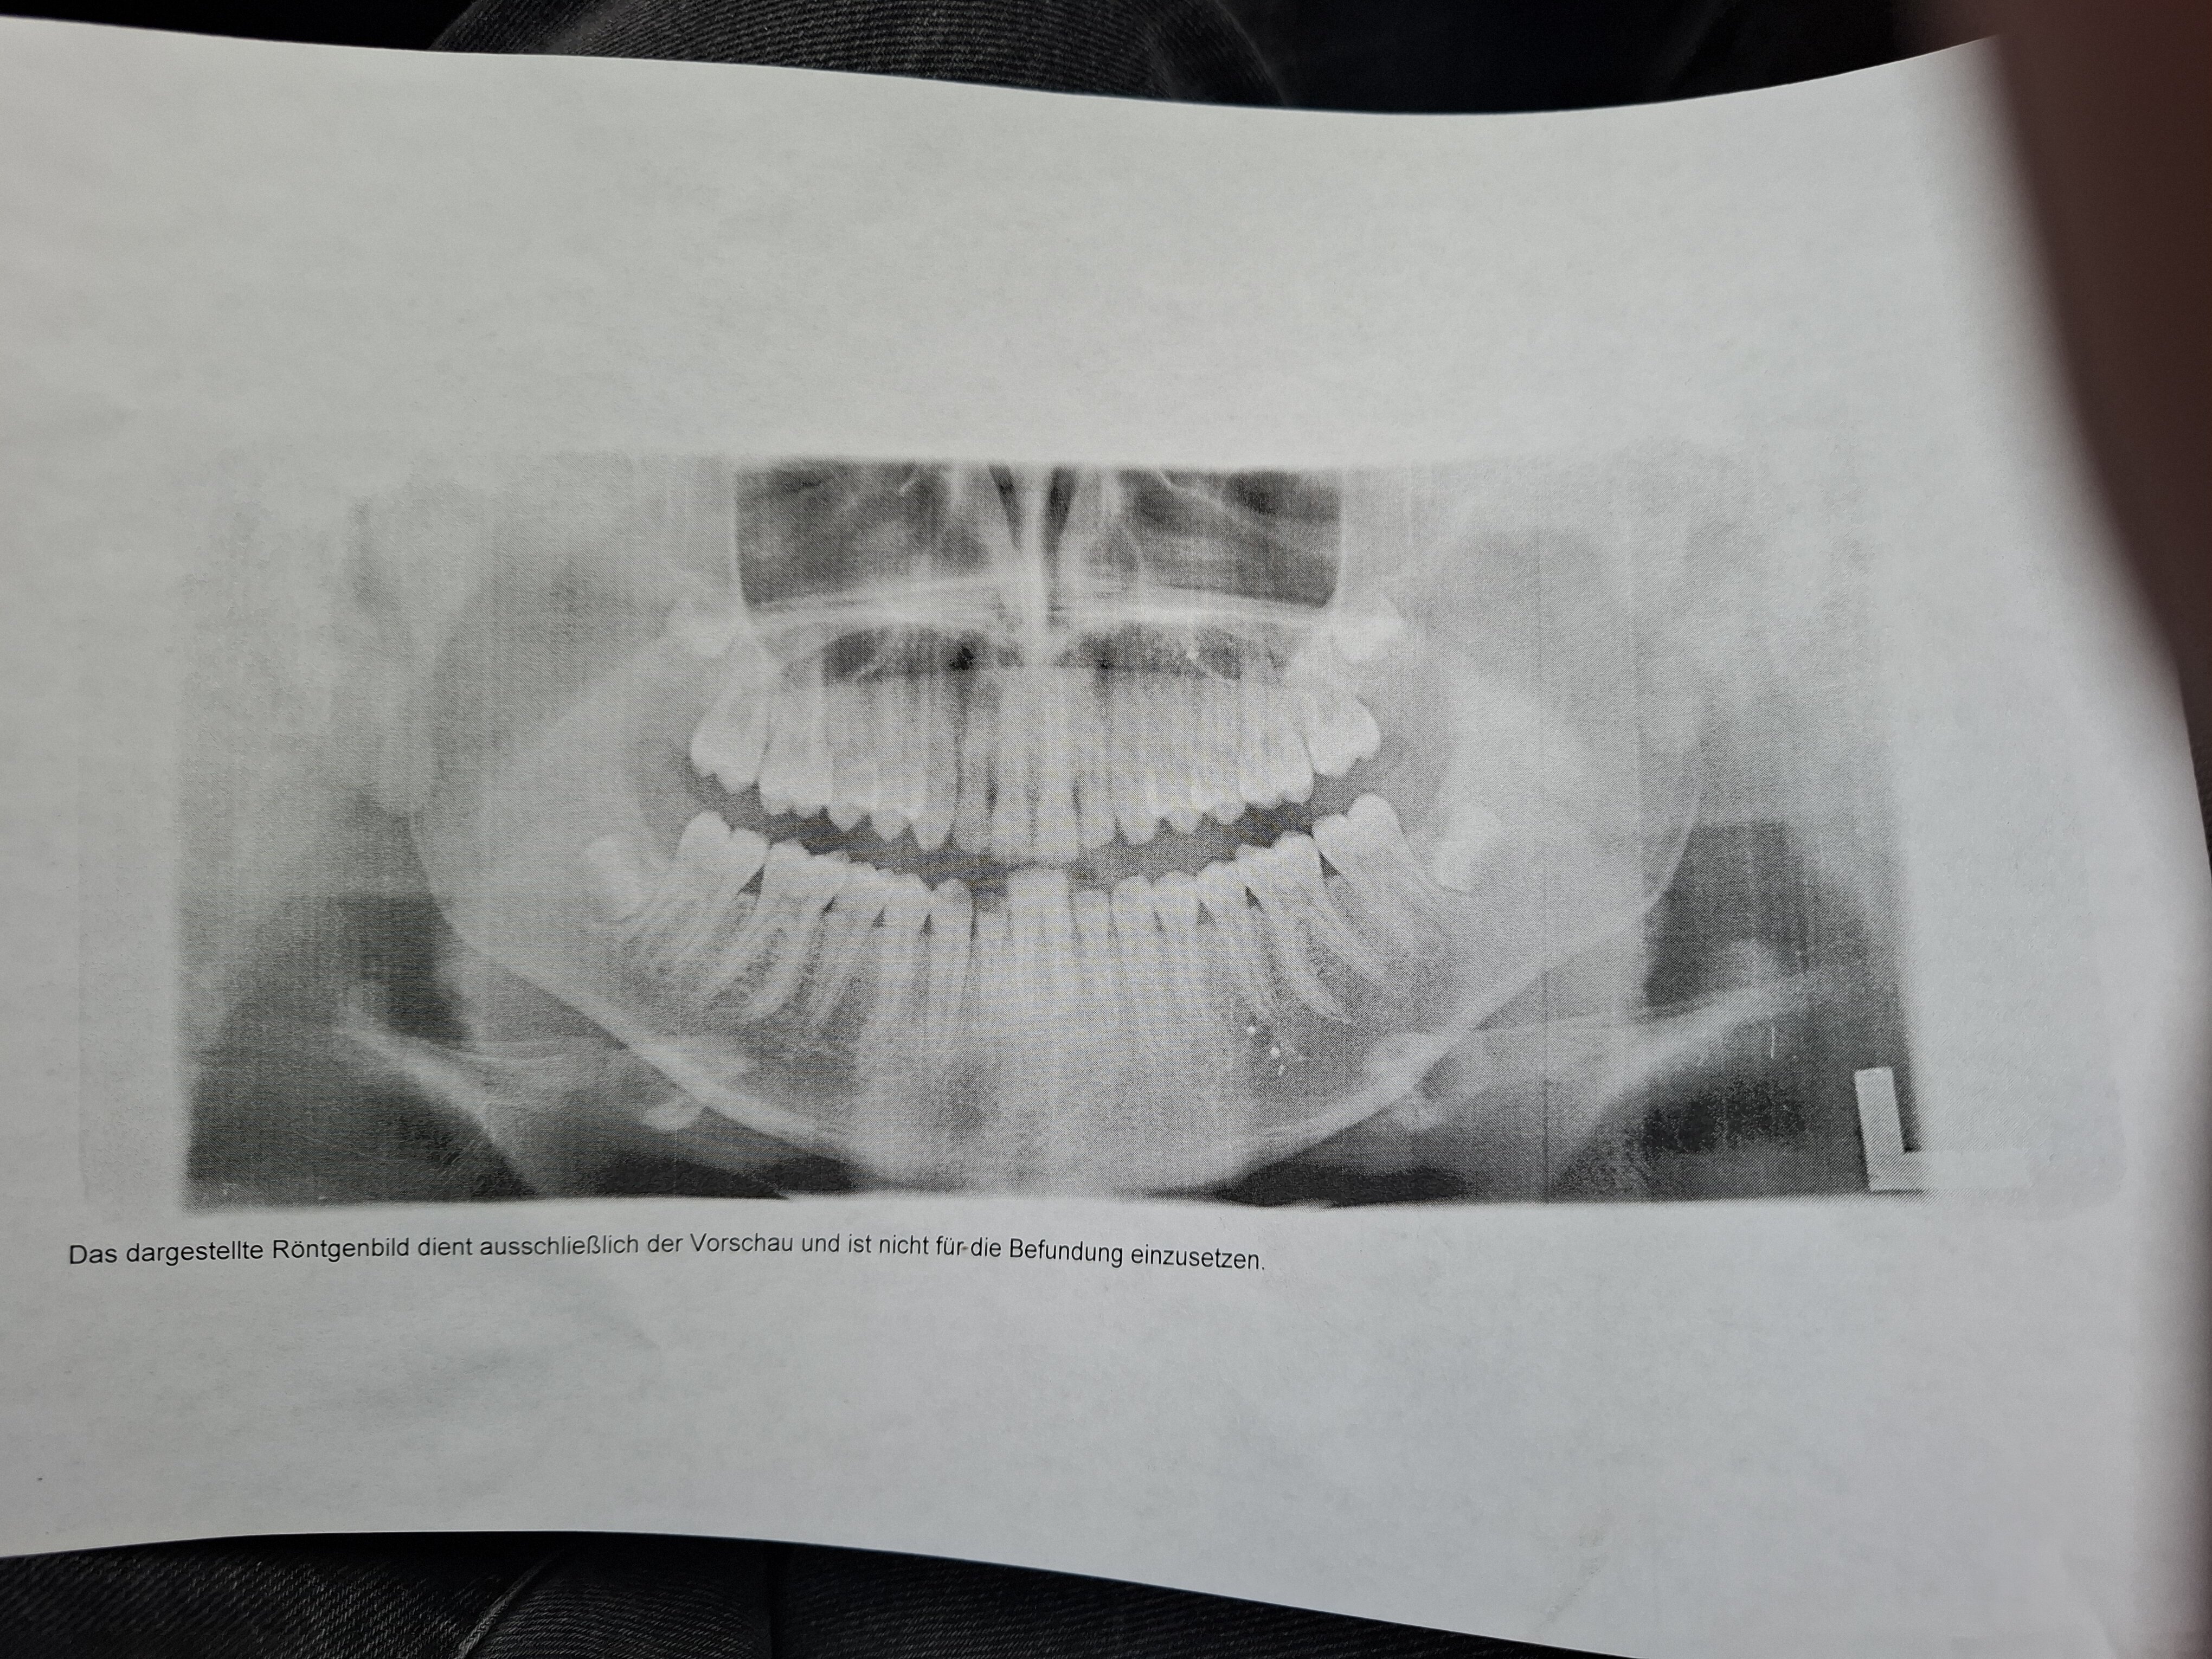

My teeth 4 years ago 2022

This is the only pic i have, they said i haf very good teeth.

the wisdom teeth are also looking good.

So no need for a removal surgery.

Idk a lot about teeth, so i would apreciate some input.